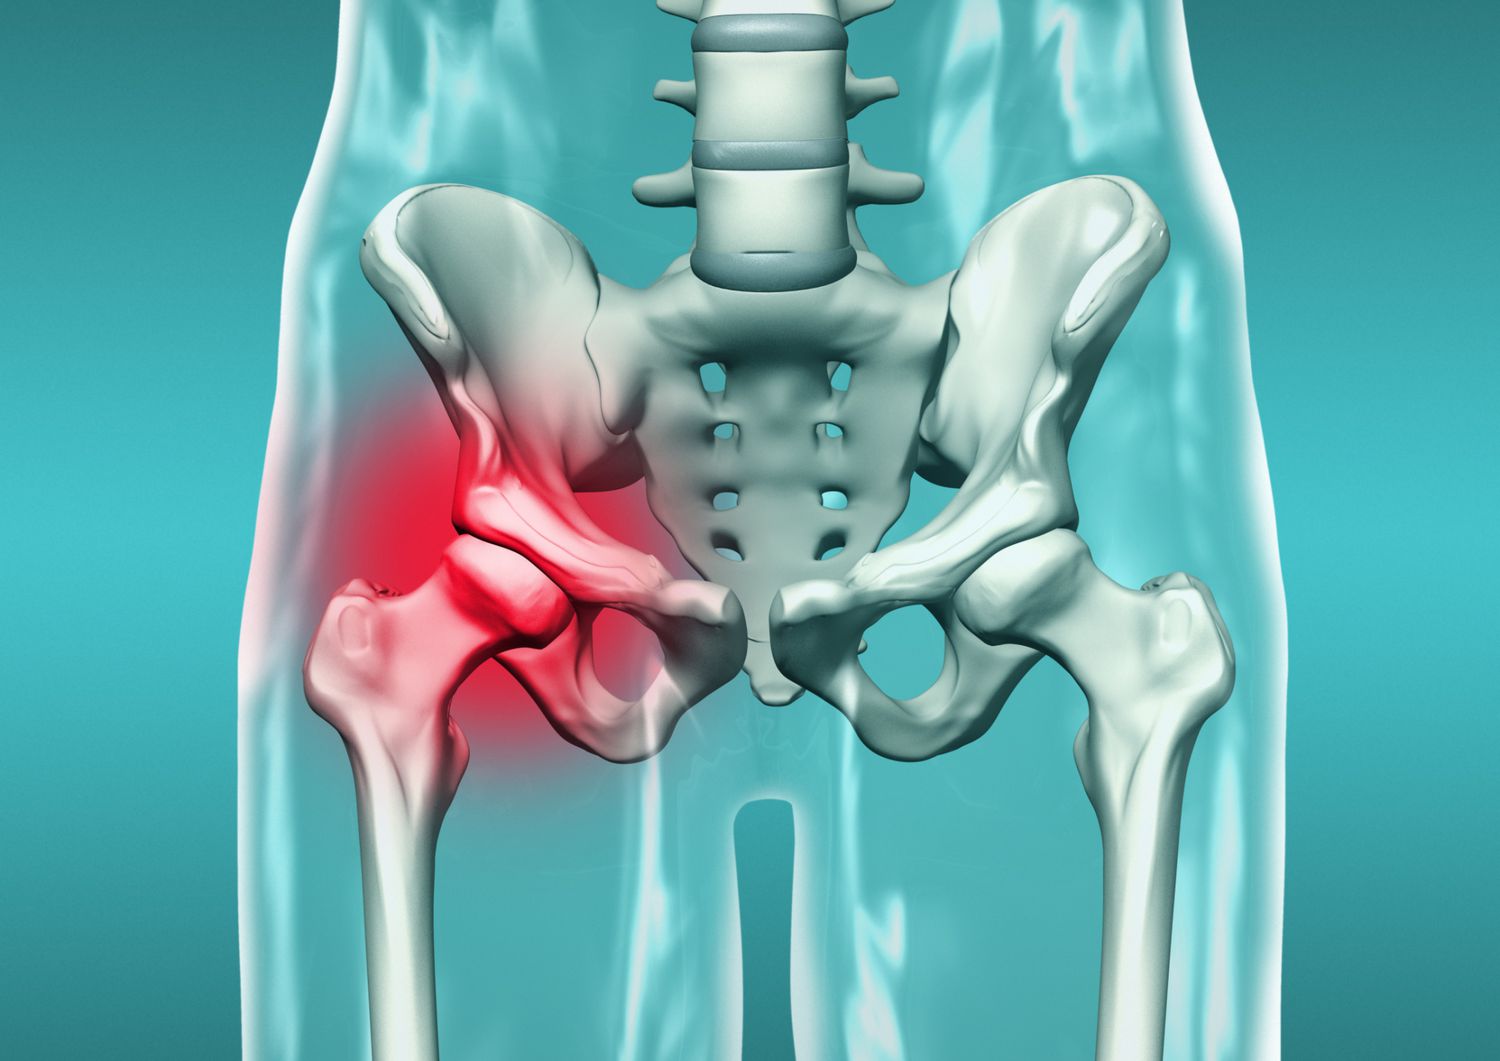

Kalça Kırığı Nedir?

Kalça bölgesindeki kemiklerin birinin veya birkaçının kırılması durumunu ifade eder. Kalça kırığı genellikle yaşlılık, düşme, travma veya osteoporoz gibi faktörler sonucu meydana gelir. Belirtileri arasında şiddetli ağrı, hareket kısıtlılığı ve şişlik yer alır. Tedavi genellikle cerrahi müdahale veya konservatif yöntemlerle yapılır. Rehabilitasyon süreci önemlidir. Komplikasyonlar önlenmezse, yaşam kalitesini olumsuz etkileyebilir.